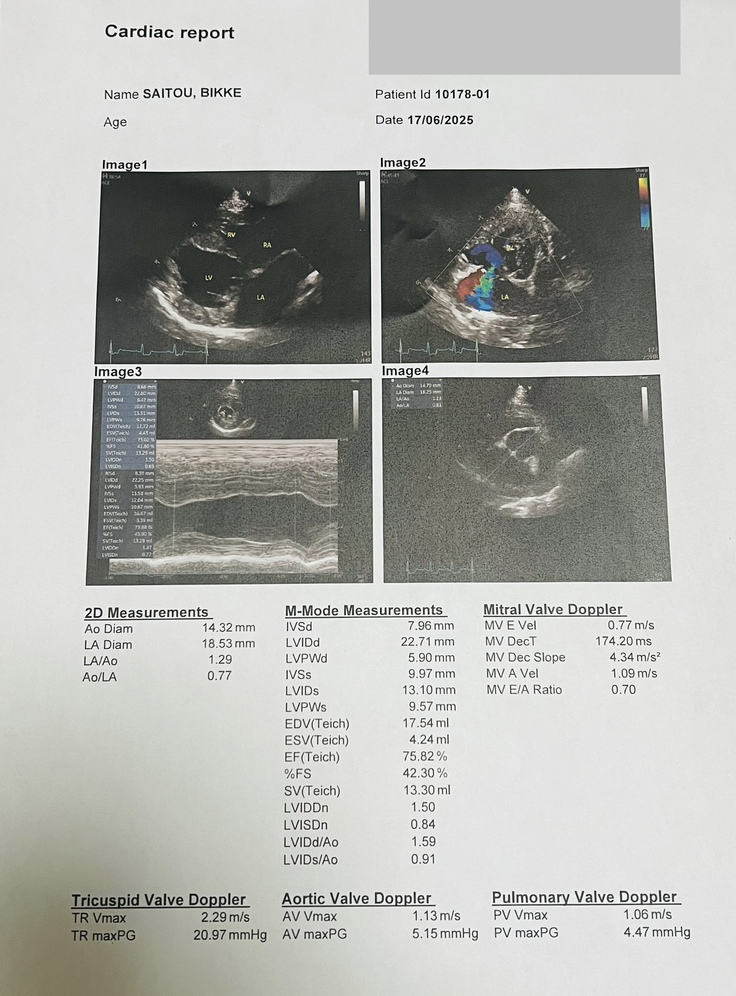

6月17日(火)、ビッケは三ヶ月検診を受けました。

診察の結果、経過は順調で、血栓の予防薬も心臓の薬もすべてやめることができました。

一部逆流は認められましたが、心臓肥大もなく経過観察となりました。